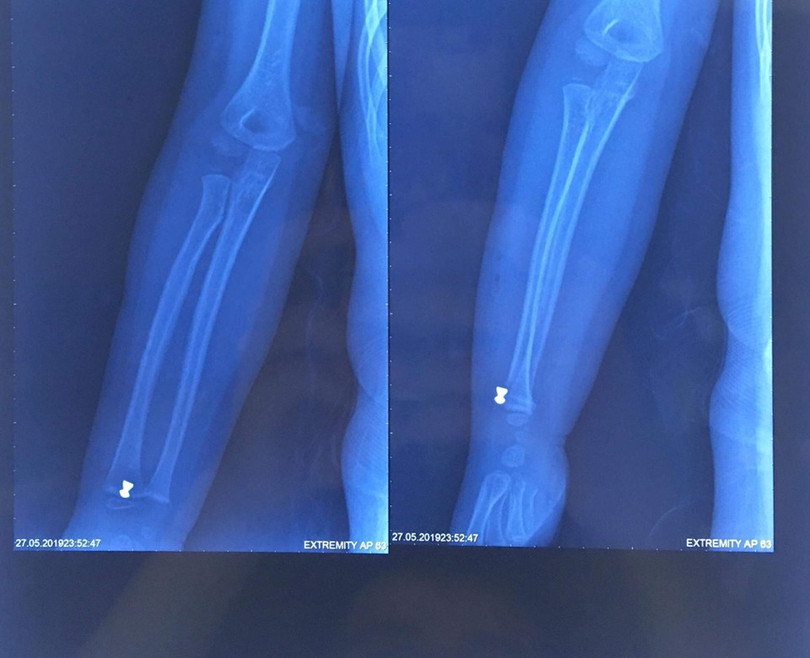

Trước đó, ngày 27/5, bé N.H.K, 5 tuổi ở Sóc Sơn, Hà Nội, được chuyển đến cấp cứu tại Bệnh viện Xanh Pôn trong tình trạng cẳng tay phải bị thương do hỏa khí. Gia đình bé cho biết, trong khi chơi trốn tìm cùng bạn, bé vô tình bị trúng đạn súng hơi do người dân bắn chuột. Gia đình đã đưa bé đến cấp cứu tại Bệnh viện Đa Khoa Sóc Sơn và sau đó là Bệnh viện Xanh Pôn. Tại đây, các bác sĩ đã khám và làm các chỉ định cận lâm sàng cho bé. Kết quả chụp XQ cho thấy, cẳng tay phải của cháu bị găm dị vật 0.5 cm, nên ngay lập tức, bé được chỉ định mổ cấp cứu để lấy dị vật.